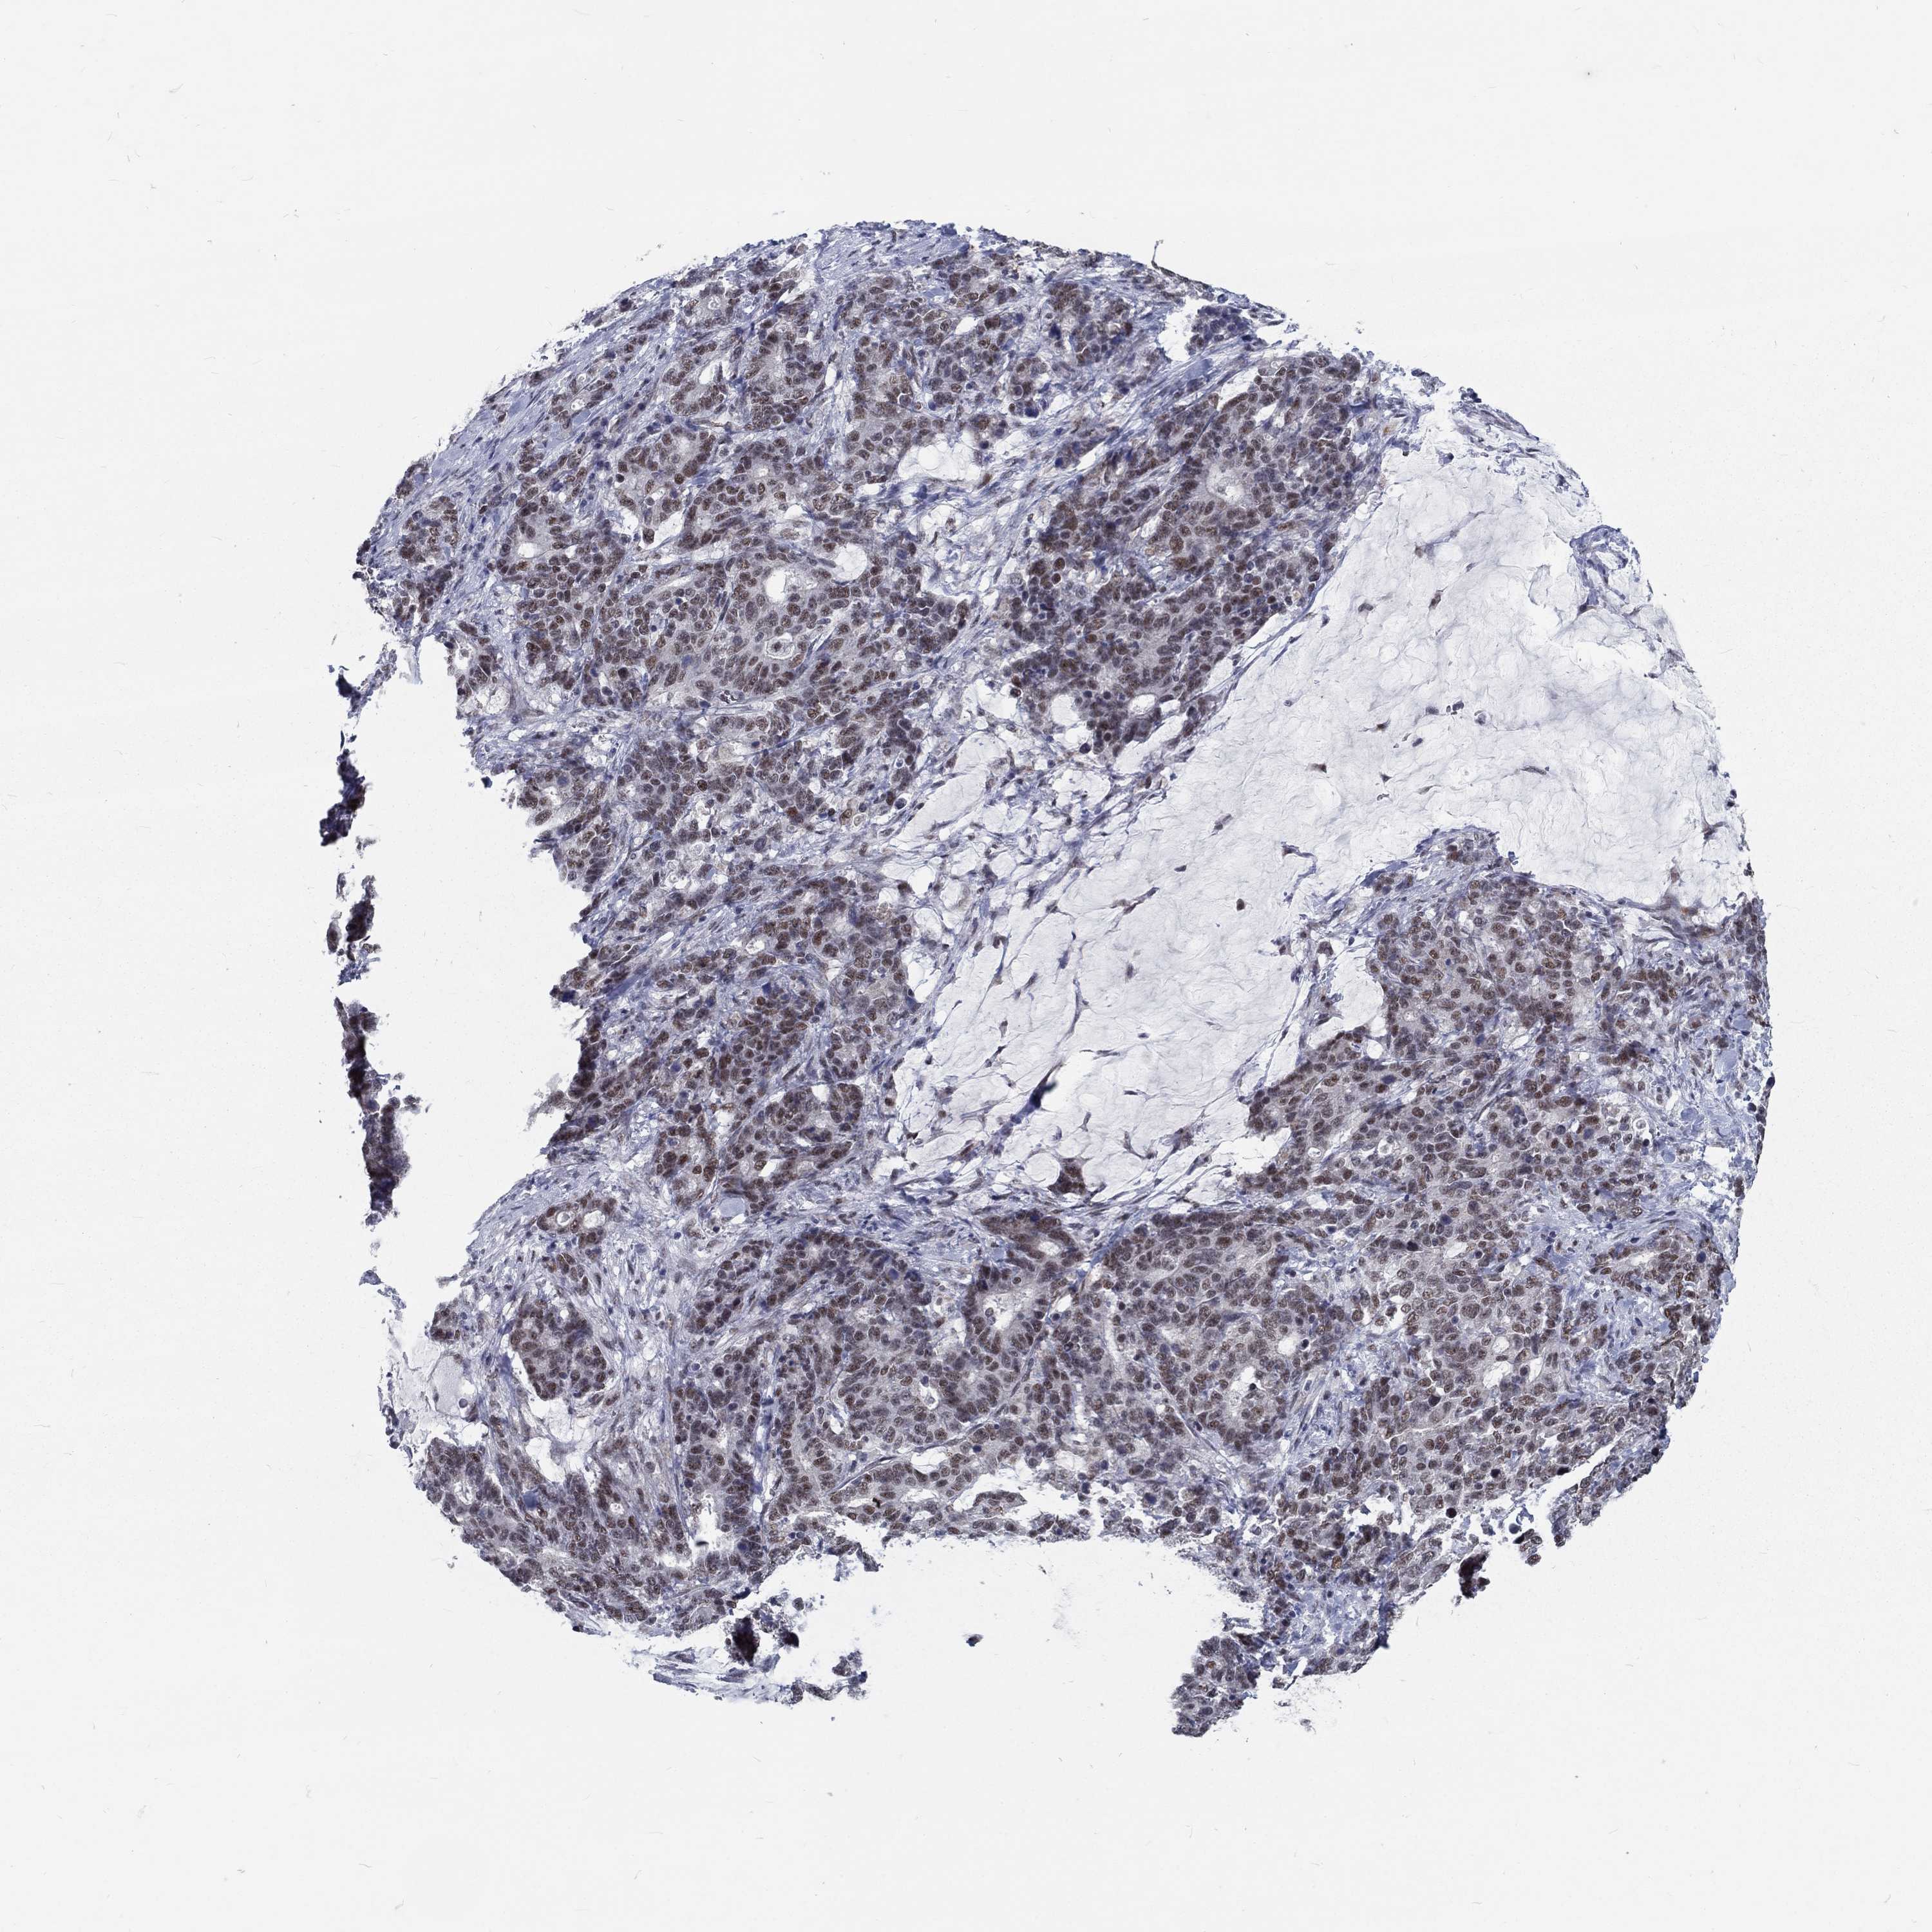

STOMACH CANCER - Protein expressioni

A mouse-over function shows sample information and annotation data. Click on an image to view it in a full screen mode. Samples can be filtered based on level of antibody staining by selecting one or several of the following categories: high, medium, low and not detected. The assay and annotation is described here.

Antibody stainingi

Antibody staining in the annotated cell types in the current human tissue is reported as not detected, low, medium, or high, based on conventional immunohistochemistry profiling in selected tissues. This score is based on the combination of the staining intensity and fraction of stained cells.

Each image is clickable and will lead to virtual microscopy that enables deeper exploration of all samples and also displays staining intensity scores, fraction scores and subcellular localization as well as patient and tissue information for each sample.

Antibody HPA077591

Staining

High

Medium

Low

Not detected

Intensity

Strong

Moderate

Weak

Negative

Quantity

>75%

75%-25%

<25%

None

Location

Nuclear

Cytoplasmic/membranous

Cytoplasmic/membranous,nuclear

Adenocarcinoma, NOS

Adenocarcinoma, High grade